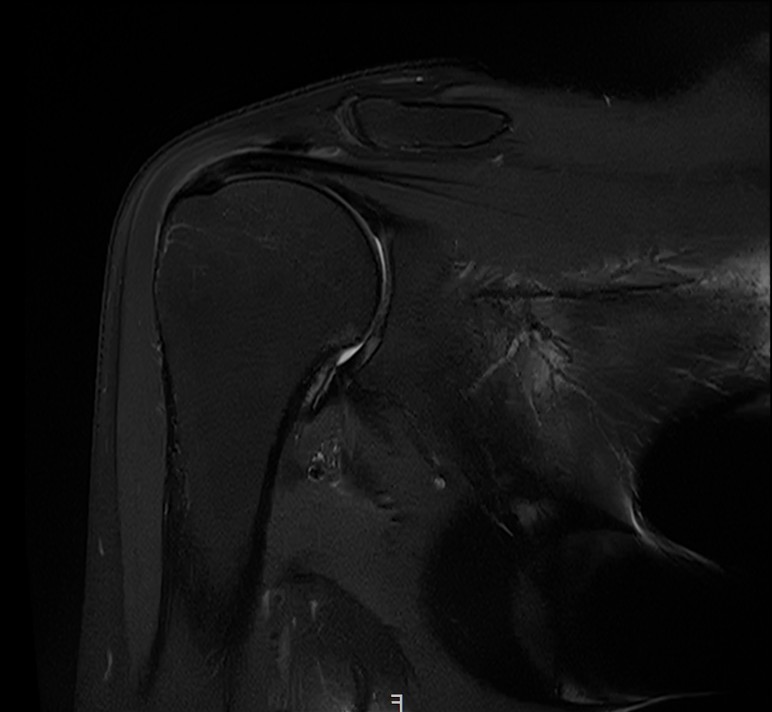

X-ray와 MRI, 초음파 검사를 시행했습니다.

진단 결과:

- ✓석회성건염: 극상건에 약 1.4cm 석회 (휴지기)

- ✓회전근개 관절면측 부분파열: 약 40%

두 가지 문제가 동시에 있었습니다.

MRI와 초음파 검사 결과:

- ✓관절면측 부분파열: 약 50%

- ✓점액낭면측 부분파열: 약 35%, 인대 얇아짐 동반

- ✓25년간 반복 사용으로 인한 퇴행성 변화 동반

양쪽 모두 손상된 복합 파열이었습니다.